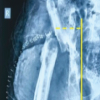

A 48-year-old male presented to us with 1½-year-old posterior hip dislocation (Fig. 1) following a road traffic accident.

Figure 1: Preoperative plain radiograph showing posterior dislocation of the left hip.